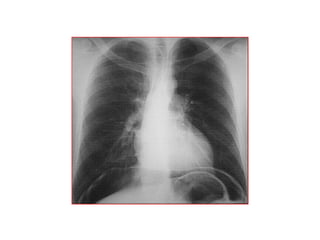

 Phim ngöïc ñöùng thaúng: tìm lieàm hôi töï do

döôùi cô hoaønh, beänh lí ñaùy phoåi..